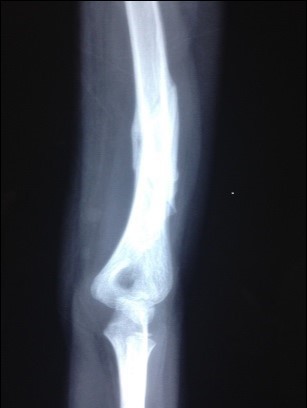

Table 1 below serve to summarize the characteristics of the patient population and the mean time for fracture union. Figure 1 and Figure 2 showed serial radiological appearance of one of the patients with upper limb delayed fracture consolidation of mid-shaft of the humerus despite casting for 5 weeks in a public hospital. Figure 2 was taken after LLLT administration showing not only obvious solid bony healing, but also very good re-modelling.

Figure 2.Same patient after LLLT administration. Notice the fracture ends re-modelled nicely and fracture had solidly healed